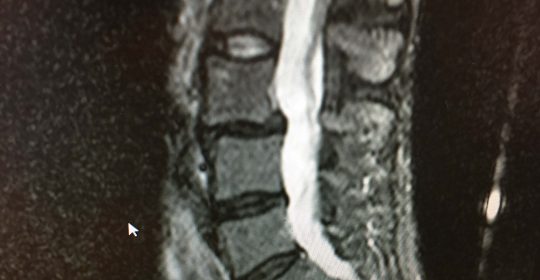

Ο ακτινολογικός έλεγχος έδειξε την ύπαρξη σπονδυλολίσθησης χωρίς σπονδυλόλυση στο επίπεδο Ο3-Ο4.

Μαγνητική Τομογραφία (1.12.2016) της Ο.Μ.Σ.Σ.-Ακολουθία Τ2 και Τ1

Οβελιαία λήψη – τομή (α,β,γ) Παρατηρείται σπονδυλολίσθηση του 3ου, επί του 4ου οσφυϊκού σπονδύλου. Οι μεσοσπονδύλιοι δίσκοι Ο3-Ο4, Ο4-Ο5, Ο5-Ι έχουν υποστεί εκφύλιση που έχει προκαλέσει απώλεια του ύψους των, με επακόλουθο την αντίστοιχη στένωση των μεσοσπονδυλίων διαστημάτων. Η εκφύλιση είναι εντονότερη στον μεσοσπονδύλιο δίσκο Ο3-Ο4, όπου και η μεσοσπονδύλιος στένωση είναι μεγαλύτερη. Η σπονδυλολίσθηση οφείλεται στην εκφύλιση του μεσοσπονδυλίου δίσκου χωρίς να υφίσταται σπονδυλόλυση.

Εγκαρσία λήψη – τομή (δ) Στο επίπεδο Ο3-Ο4, παρατηρείται ότι δεν υφίσταται σπονδυλόλυση. Δεν υπάρχει πίεση του νωτιαίου σάκου ή των νευρικών ριζών. Ο 3ος οσφυϊκός έχει μετατοπισθεί προσθίως επί του 4ου οσφυϊκού σπονδύλου.